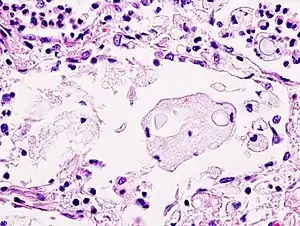

Biopsy

A special stain may be needed to see the cryptococcus capsule.[33]

Mucicarmine stain: bright pink cryptococcosis capsule[33]

Field stain: thick cryptococcosis capsule

H&E stain: histiocytic penumonia_Alcian_blue-PAS.jpg.webp)